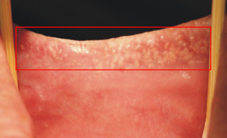

白水腫(Leukoedema)的臨床特徵是頰黏膜呈現白色至灰白色的皺紋,而當黏膜被撐開時,這些皺紋會消失不見,放開後又會回復皺摺狀。白水腫發生的原因未明,但是常見於抽菸者的口腔中。由於白水腫是一種良性的口腔黏膜變化,一般不需要做治療,但是若有抽菸的習慣時,則是建議戒除抽菸的習慣喔!